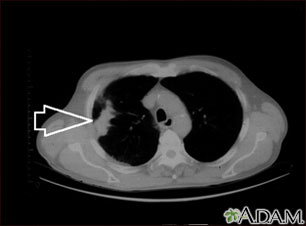

Lung mass, right lung - CT scan

This is a CT scan of the upper chest showing a mass in the right lung (seen on the left side of the picture).